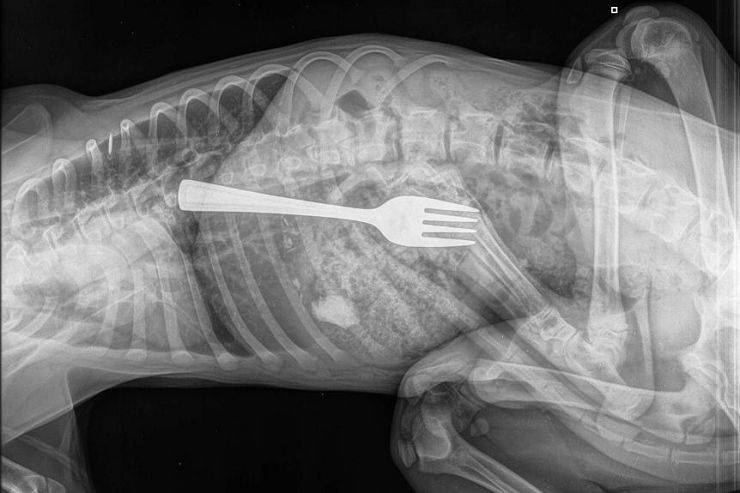

I veterinari erano increduli e solo dopo aver effettuato una radiografia hanno accertato che Dustin aveva veramente mangiato una forchetta.

“Se non avessi avuto la mia formazione, avrei pensato che qualcuno avesse manipolato la radiografia”, ha commentato il veterinario Matt Woodruff dopo aver visto la radiografia.

“Immaginate di ricevere una telefonata nella quale viene detto che: Penso che il mio cane abbia mangiato una forchetta. Una forchetta? Davvero? Siete sicuri? È di plastica? O di metallo?'”, racconta il veterinario che ha poi vivamente consigliato ai padroni di portarlo in clinica, sostenendo che si trattava di un’emergenza assoluta.